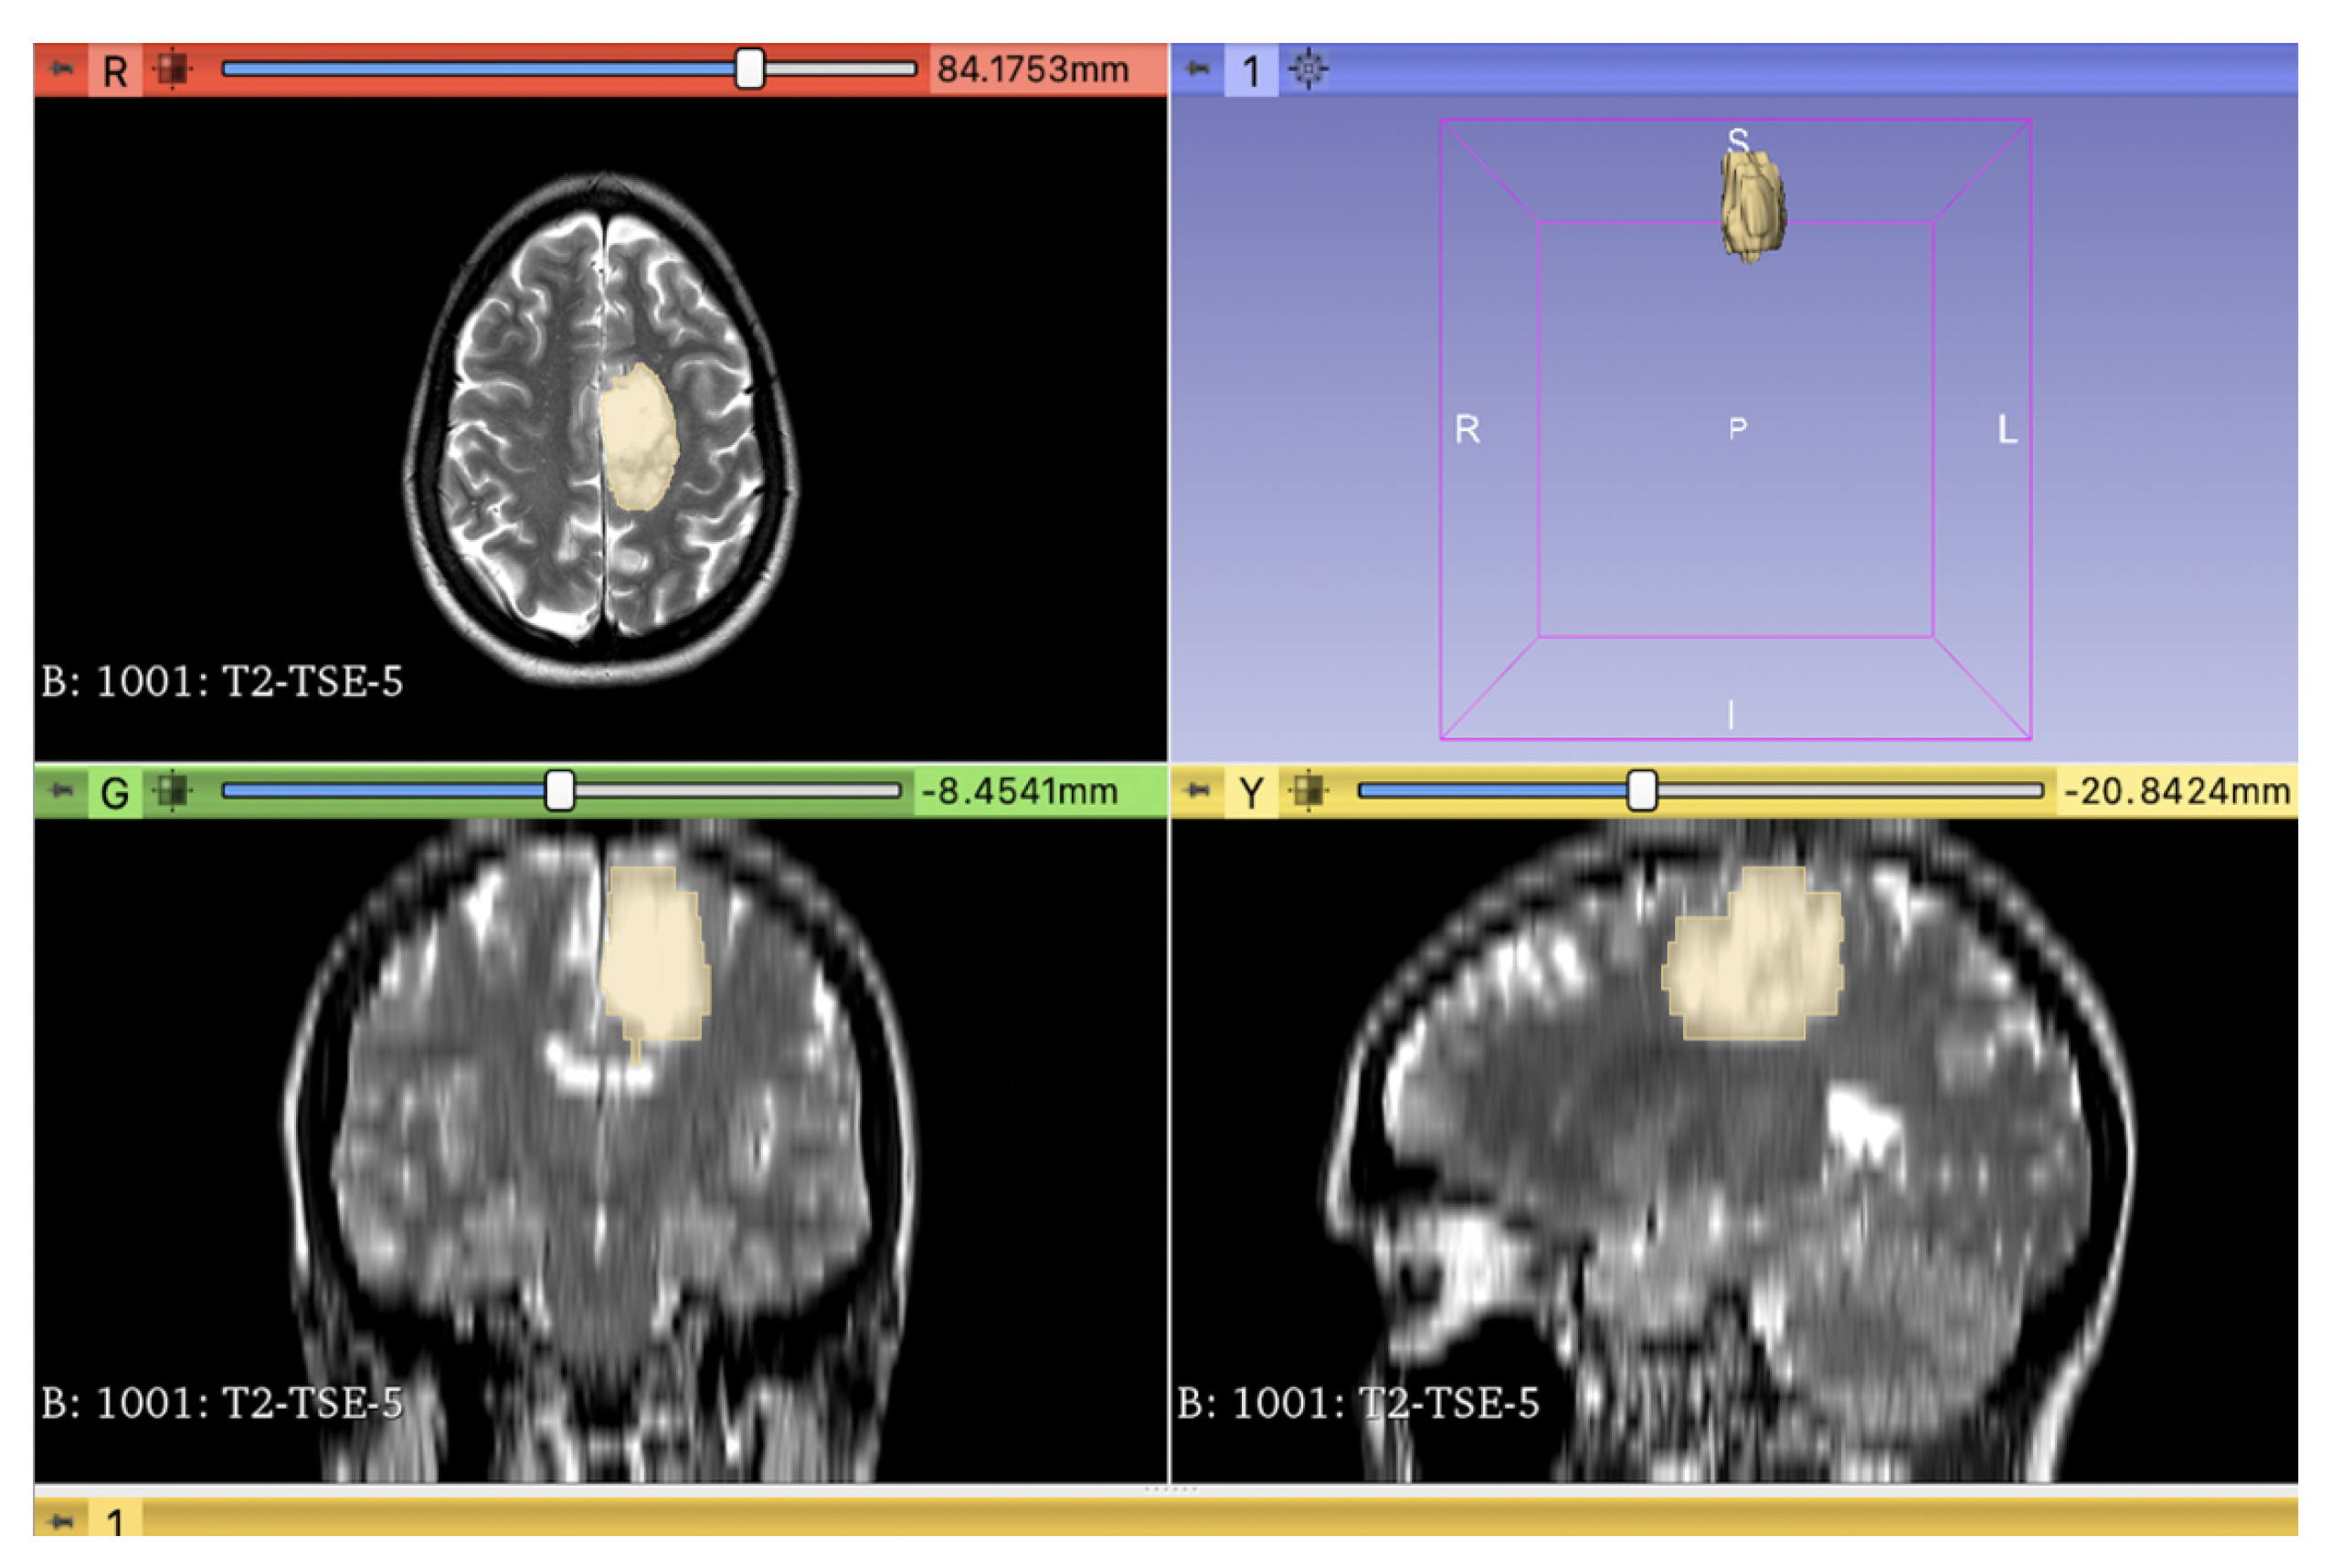

2. Materials and Methods

2.1. Radiomics